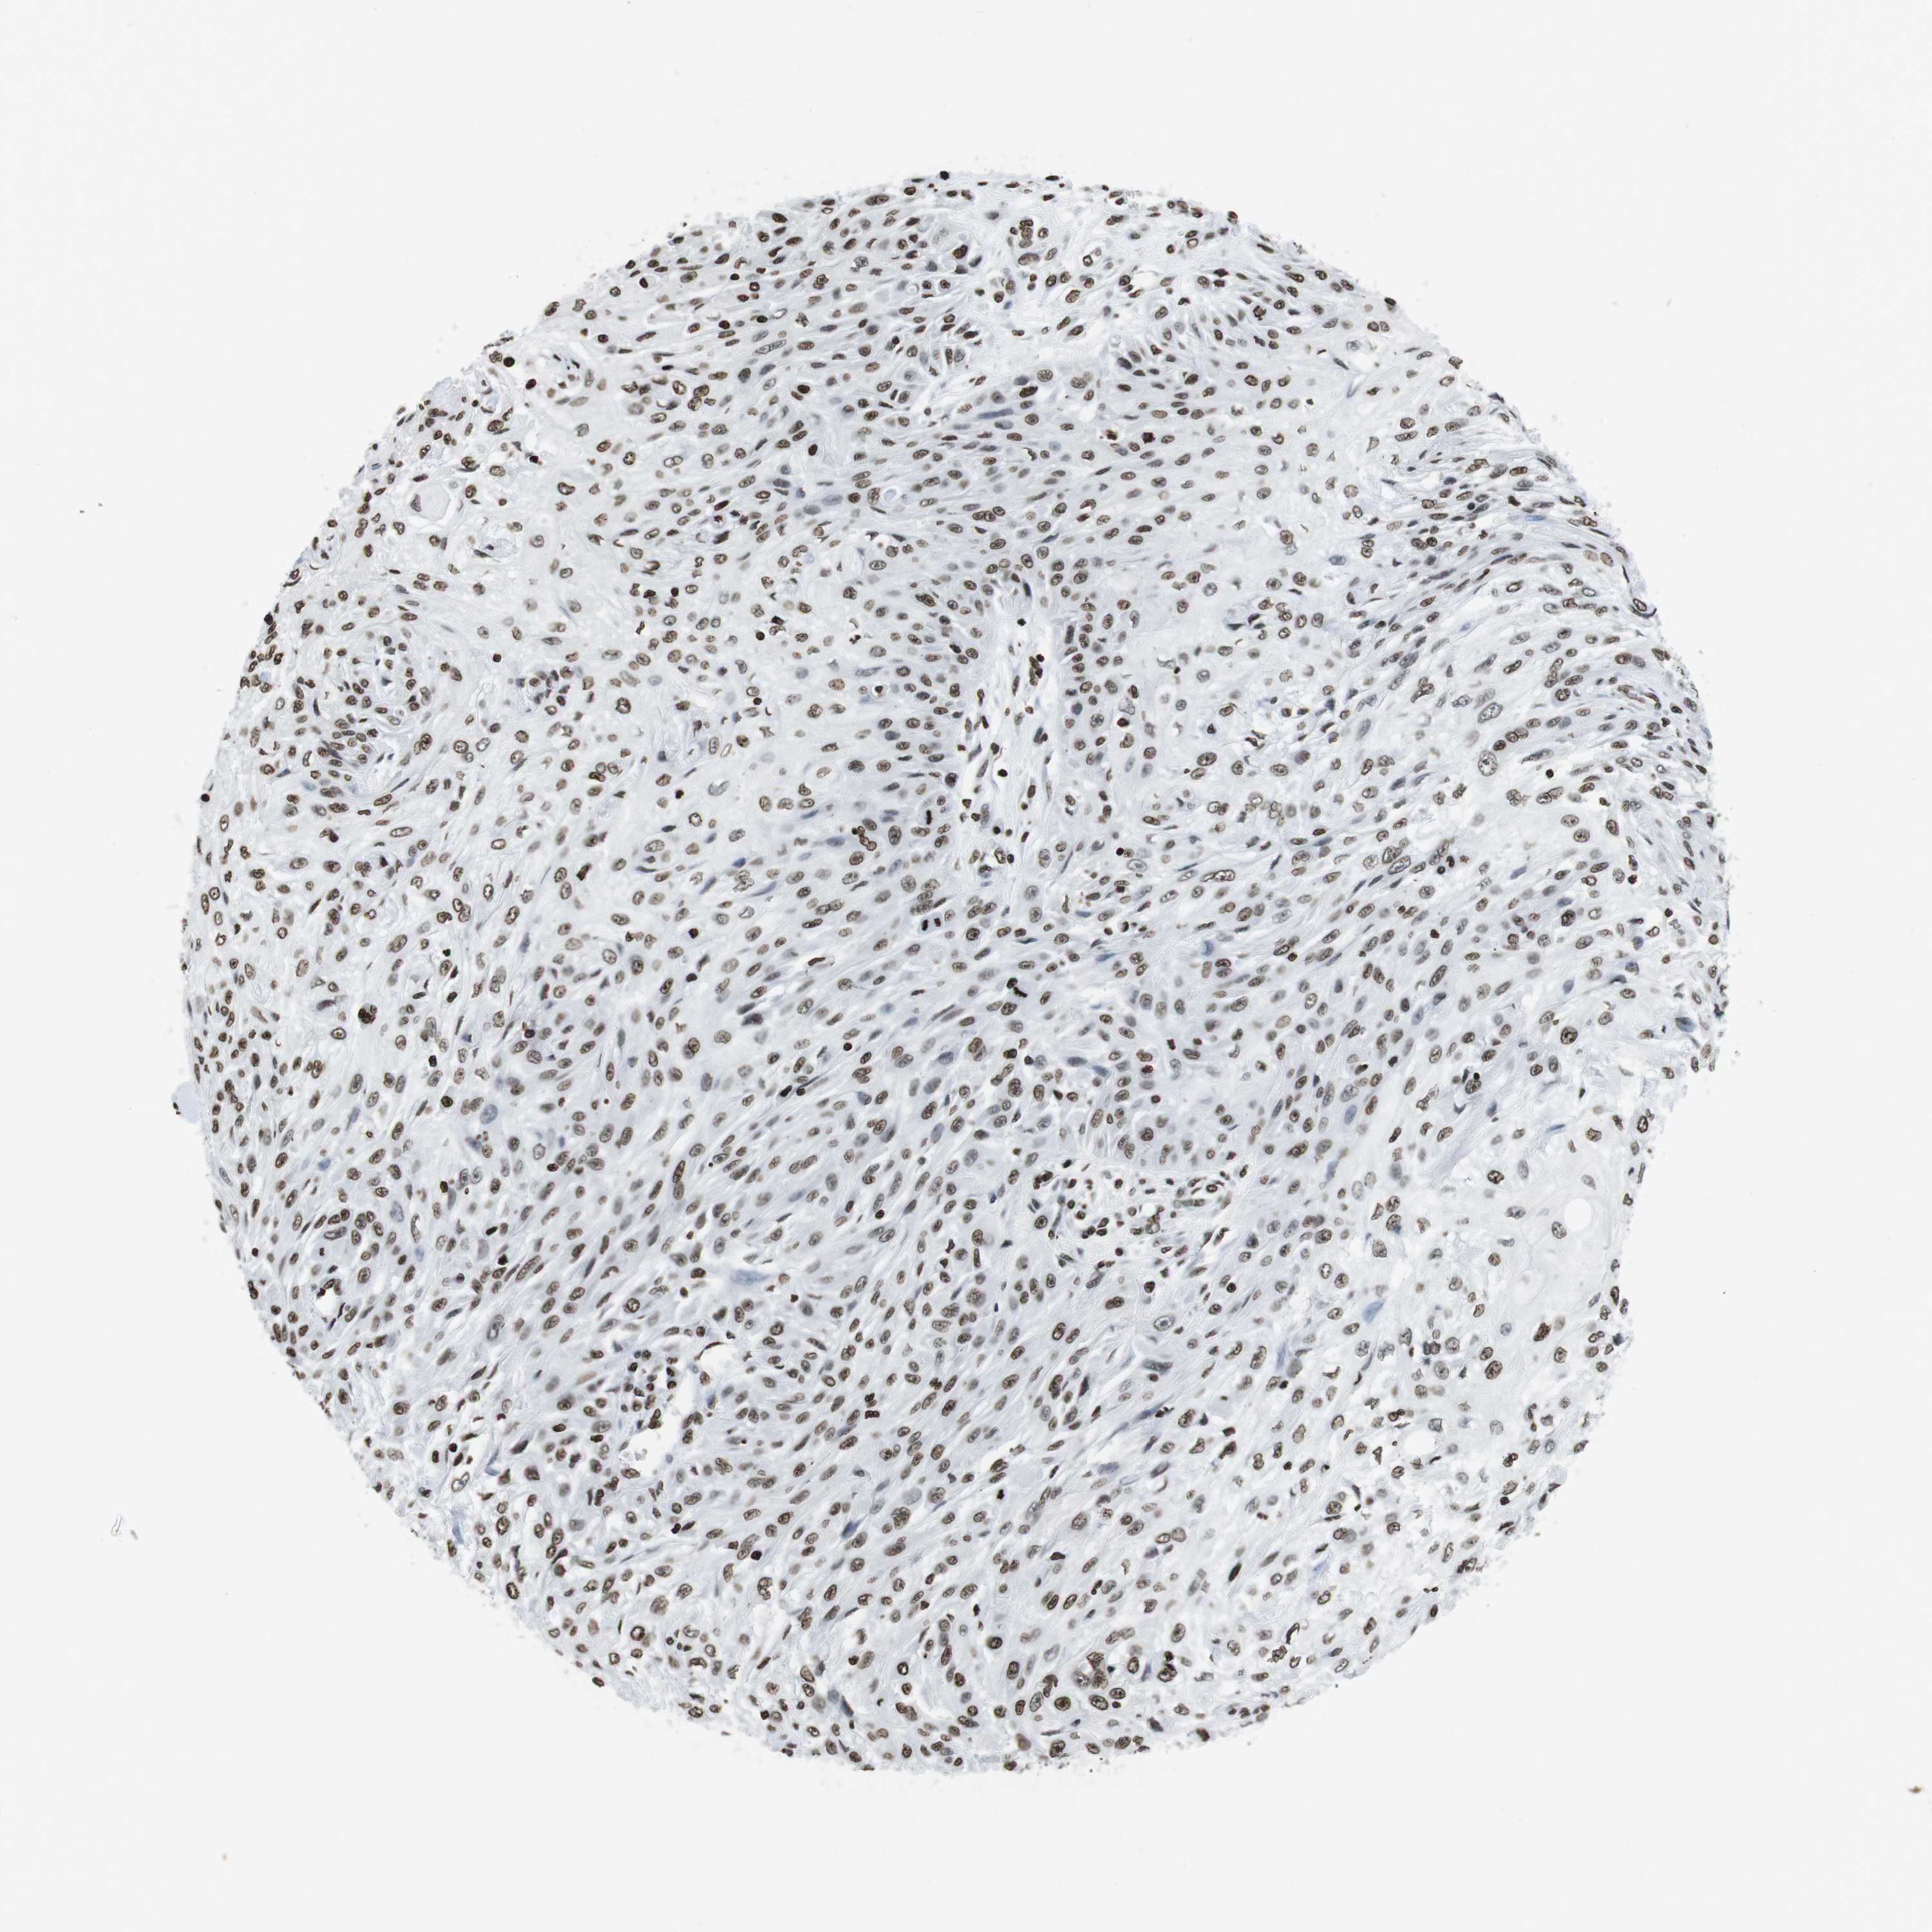

SKIN CANCER - Protein expressioni

A mouse-over function shows sample information and annotation data. Click on an image to view it in a full screen mode. Samples can be filtered based on level of antibody staining by selecting one or several of the following categories: high, medium, low and not detected. The assay and annotation is described here.

Antibody stainingi

Antibody staining in the annotated cell types in the current human tissue is reported as not detected, low, medium, or high, based on conventional immunohistochemistry profiling in selected tissues. This score is based on the combination of the staining intensity and fraction of stained cells.

Each image is clickable and will lead to virtual microscopy that enables deeper exploration of all samples and also displays staining intensity scores, fraction scores and subcellular localization as well as patient and tissue information for each sample.

Antibody HPA015654

Staining

High

Intensity

Strong

Quantity

>75%

Location

Nuclear

Squamous cell carcinoma in situ, NOS

Squamous cell carcinoma, NOS

Basal cell carcinoma

Adnexal tumor, benign